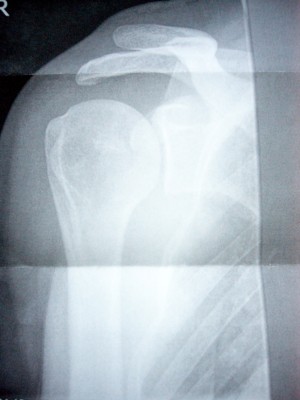

und...jetzt hat der arzt mir den zettel weggenommen, wo das draufstand. ac-sprengung auf jeden fall. das heisst, dass da. wo der oberarm oben mit dem schulterblatt und dem schlüsselbein verbunden ist, da ist es abgerissen. und nunist da ein grosser spalt, wo keiner sein sollte. sihe das schöne bild. der knochen, der da so nach oben ragt, der soll wohl mehr so weiter unten sein. und nicht oben rausgucken.

Dateianhänge:

L1030363.JPG

L1030363.JPG [ 1017.16 KiB | 3436-mal betrachtet ]